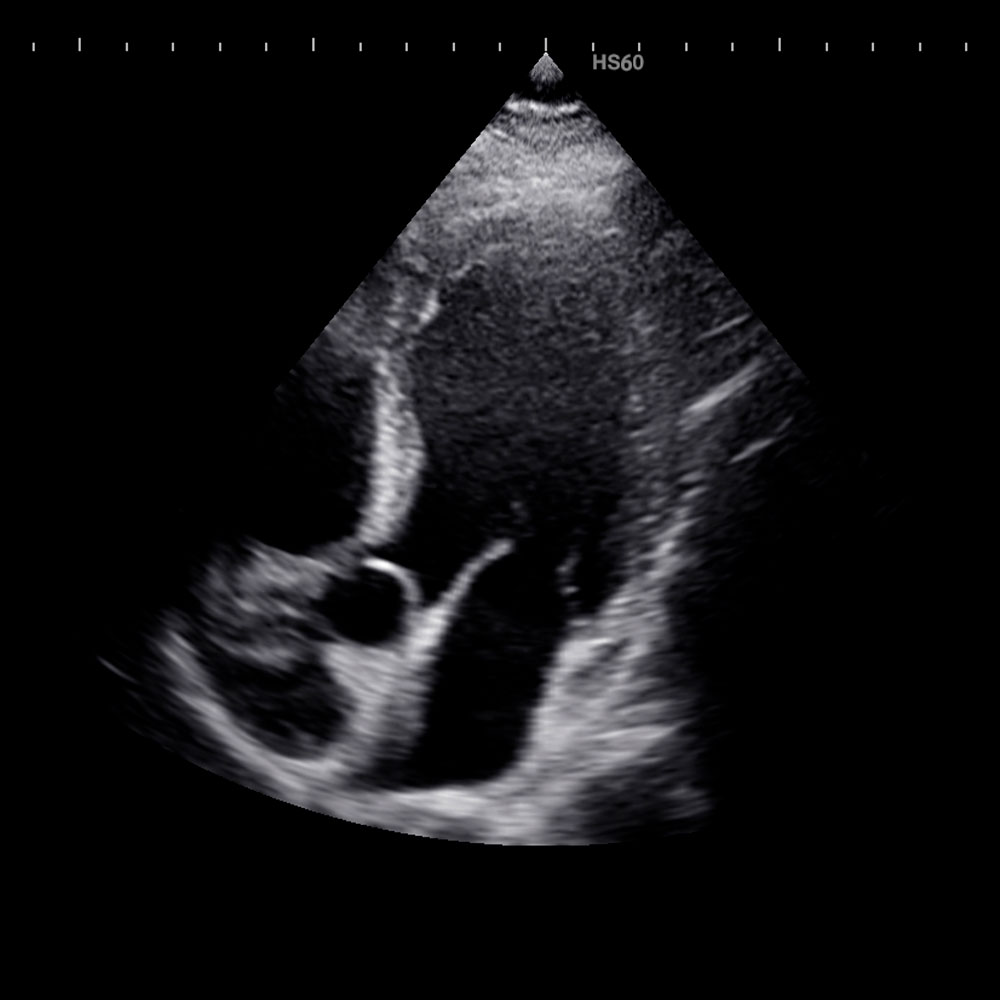

Echokardiographie

Mit der Echokardiogarphie mit Farbdoppler kann die Größe und Funktion der Herzkammern und die Funktion der Herzklappen beurteilt werden.